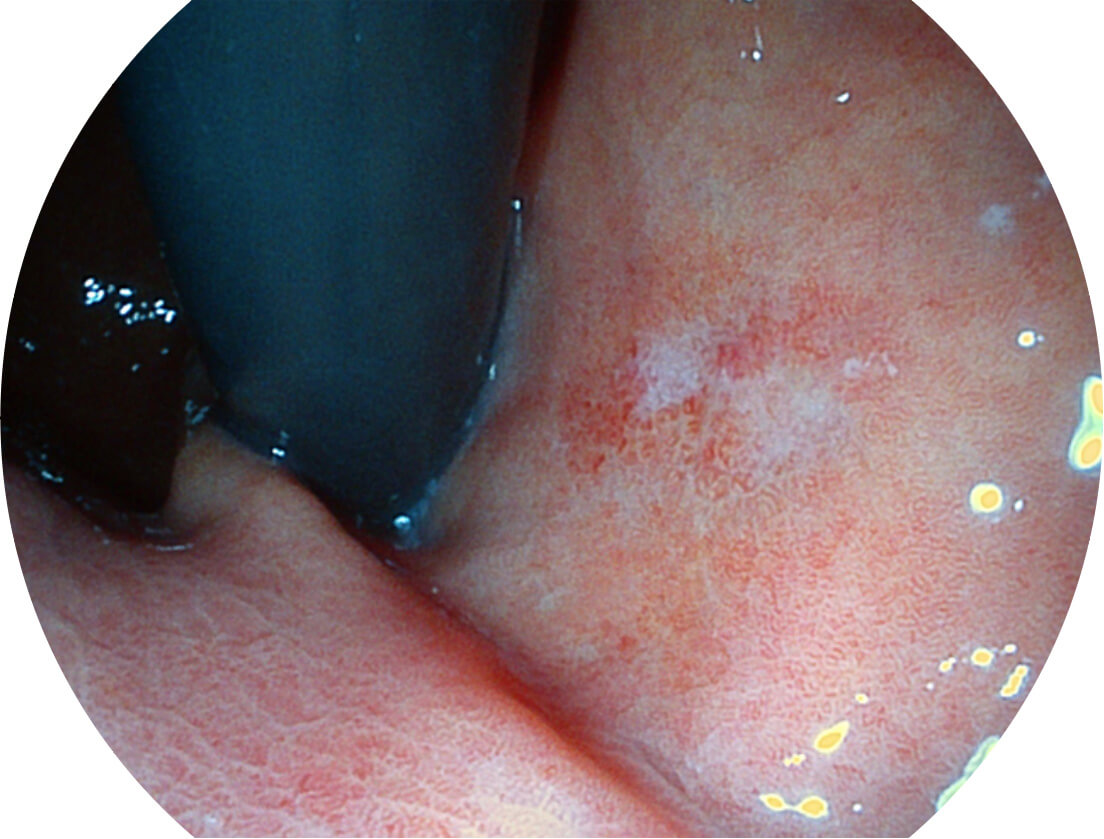

Versatile Intelligent Staining Technology, VIST

强调浅层黏膜结构的同时,保证照明亮度和提升浅层微血管与中层血管颜色对比度,病变边界更清晰。

VIST图像